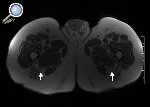

Figura 7. Paciente de 73 años que presentaba parestesias leves en el territorio peroneo de ambos lados. En las imágenes ponderadas T1 se observa aumento de grosor del nervio ciático de ambos lados a expensas de una hipertrofia del componente graso intraneural, hallazgo compatible con lipomatosis bilateral del nervio ciático (flecha).